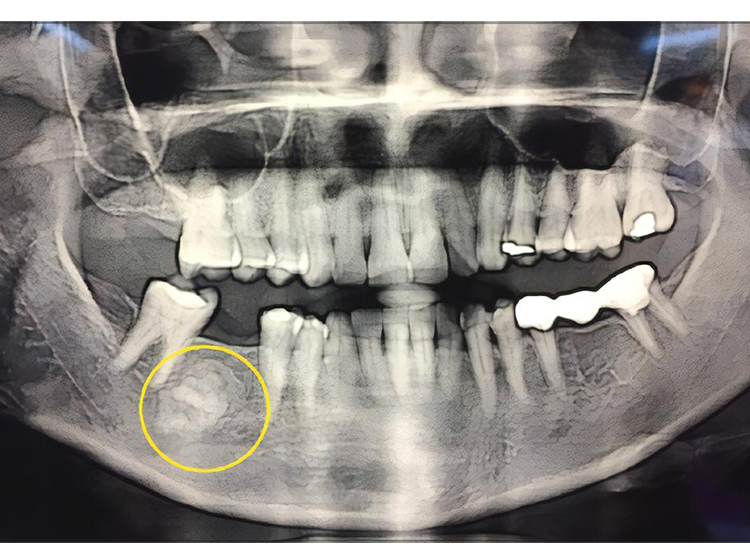

خلل التنسج العظمي الأسمنتي (COD) هو حالة خلقية حميدة في الفكين قد تنشأ من الخلايا الليفية للأربطة الداعمة للسن. لديها ثلاثة أنواع وهي خلل التنسج الملاطي حول الذروة (شائع في أولئك المنحدرين من أصل أفريقي) ، وخلل التنسج الأسمنتي العظمي البؤري (القوقازيين) ، وخلل التنسج العظمي الأسمنتي الزهري (أصل أفريقي). يحدث محيط الذروة بشكل شائع في الأسنان الأمامية للفك السفلي بينما يظهر البؤري في الغالب في الأسنان الخلفية للفك السفلي ومزهر في كل من الفك العلوي والفك السفلي في الأرباع المتعددة. تشخبص التشخيص مهم لتجنب الخلط بينه وبين مرض محيطي آخر مثل التهاب العظم المتكثف أو التهاب العظم المتكثف. طريقة التشخيص الأشعة السينية ، التصوير المقطعي المحوسب ، فحص حيوية الأسنان تشخيص متباين مرض باجيت الذي يصيب العظام ، خلل التنسج الليفي ، خراج الأسنان علاج او معاملة استراتيجية العلاج الرئيسية لخلل التنسج الأسمنتي العظمي هي تجنب ملامسة العظام المصابة بالميكروبات الفموية ، والتي تحدث في حالات أمراض اللثة الالتهابية المزمنة المرتبطة باللويحات الجرثومية للأسنان ، والنخر الذي يليه نخر اللب والأمراض المزمنة حول الذ